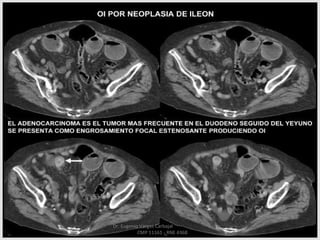

TUMORES

TUMORES BENIGNOS:

 ADENOMAS, POLIPOS Y

PAPILOMAS

 LIPOMAS

 LEIOMIOMAS

TUMORES MALIGNOS:

 LINFOSARCOMAS

 LEIOMIOSARCOMAS

 ADENOCARCINOMAS

TODOS ESTOS TUMORES

MENCIONADOS PUEDEN DAR LUGAR

A SINDROMES OBSTRUCTIVOS POR

DIFERENTES MECANISMOS COMO

OBSTRUCCION EN LA LUZ

INTESTINAL ,TORCION ,

INVAGINACION , COMPRESION

EXTRINSECA...ETC.